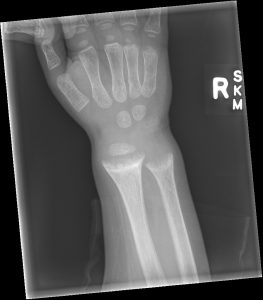

Common bone fractures: